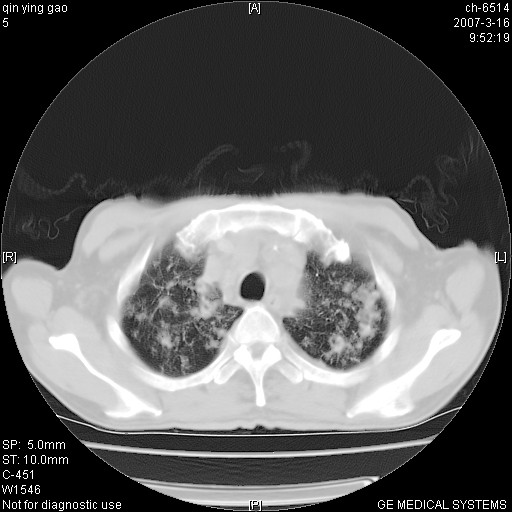

男,64岁.乏力2个月,畏寒、发热1月余。体重下降。血沉加快,白细胞不高。

两中上肺见有广泛新老不一的结节灶,并伴有纤维索条影,血沉加快,白细胞不高,首先考虑结核。

双肺以中上肺野为著斑片状.结节壮密度增高影 左上肺前段可见小类圆钙化灶 纵隔淋巴结无明显肿大

双肺可见大小不等结节状密度增高影,密度不均,分布不均(双肺上叶为著),亚急性血行播散性肺结核.

(本例特征:以大小不等结节为主,主要分布在双上肺,并部分病灶融合成较大结节,期间搀杂诸多细小结节。从病灶特点与分布形式分析,更趋向于感染。)

男,64岁.乏力2个月,畏寒、发热1月余。体重下降。血沉加快,白细胞不高。 双肺可见大小不等结节状密度增高影,密度不均,分布不均(双肺上叶为著),亚急性血行播散性肺结核.

中上肺野密布棉团状影,以胸膜下区为界,边缘模糊,可能是小叶或腺泡渗出及实变。全肺野弥漫分布网线样影及细小粟粒样影,可能是细支气管炎及间质内炎症。综合分析应首先考虑气道播散性感染,而肺内多处斑点性钙化,强烈提示陈旧结核复发并支气管播散。建议详细讯问病史